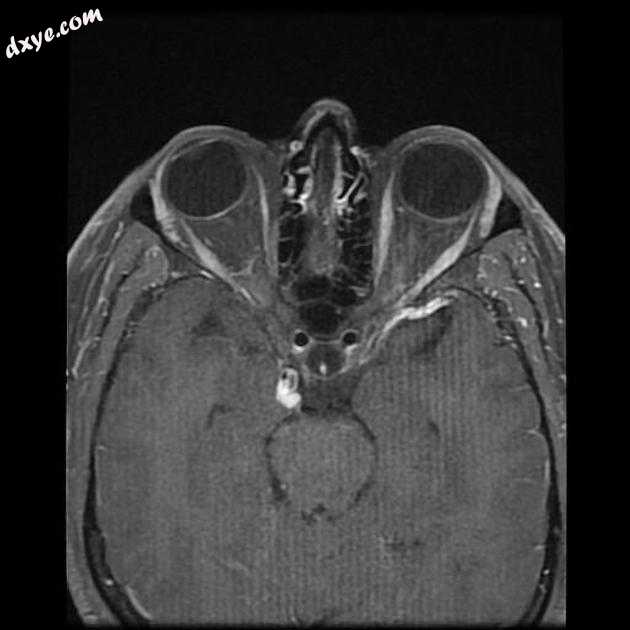

Axial T1 C+

9.jpeg

MRI 序列显示右侧颈内动脉的部分血栓囊状动脉瘤位于 C6/7 节段的交界处,大小为 11 x 7 毫米,颈部为 2.5 毫米,压迫动眼神经 (III) 的相邻节段,在 T1 上清晰可见和 FIESTA 序列。

位于 C6/7 交界处的右侧颈内动脉部分血栓囊状动脉瘤的 MRI 特征,压迫同侧动眼神经 (III)。